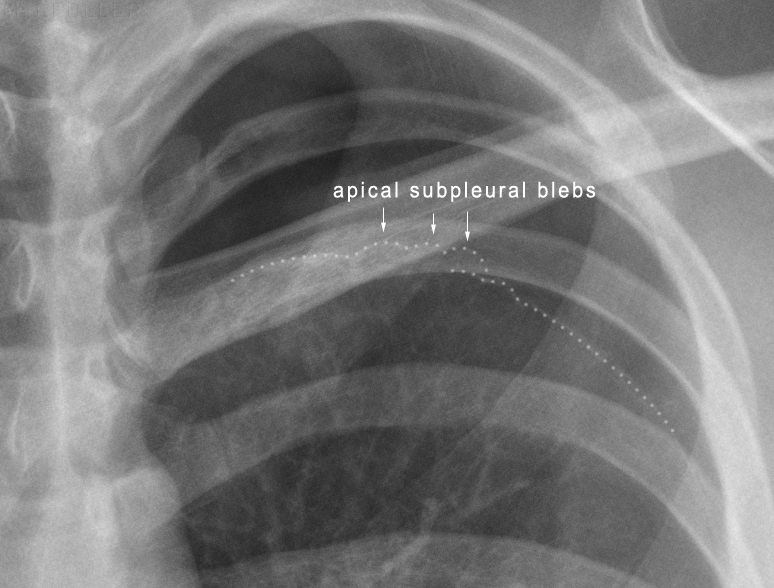

Tall, thin males around the age of 20

Smoking

Deborah Dalmeida MD

Primary spontaneous Pneumothorax